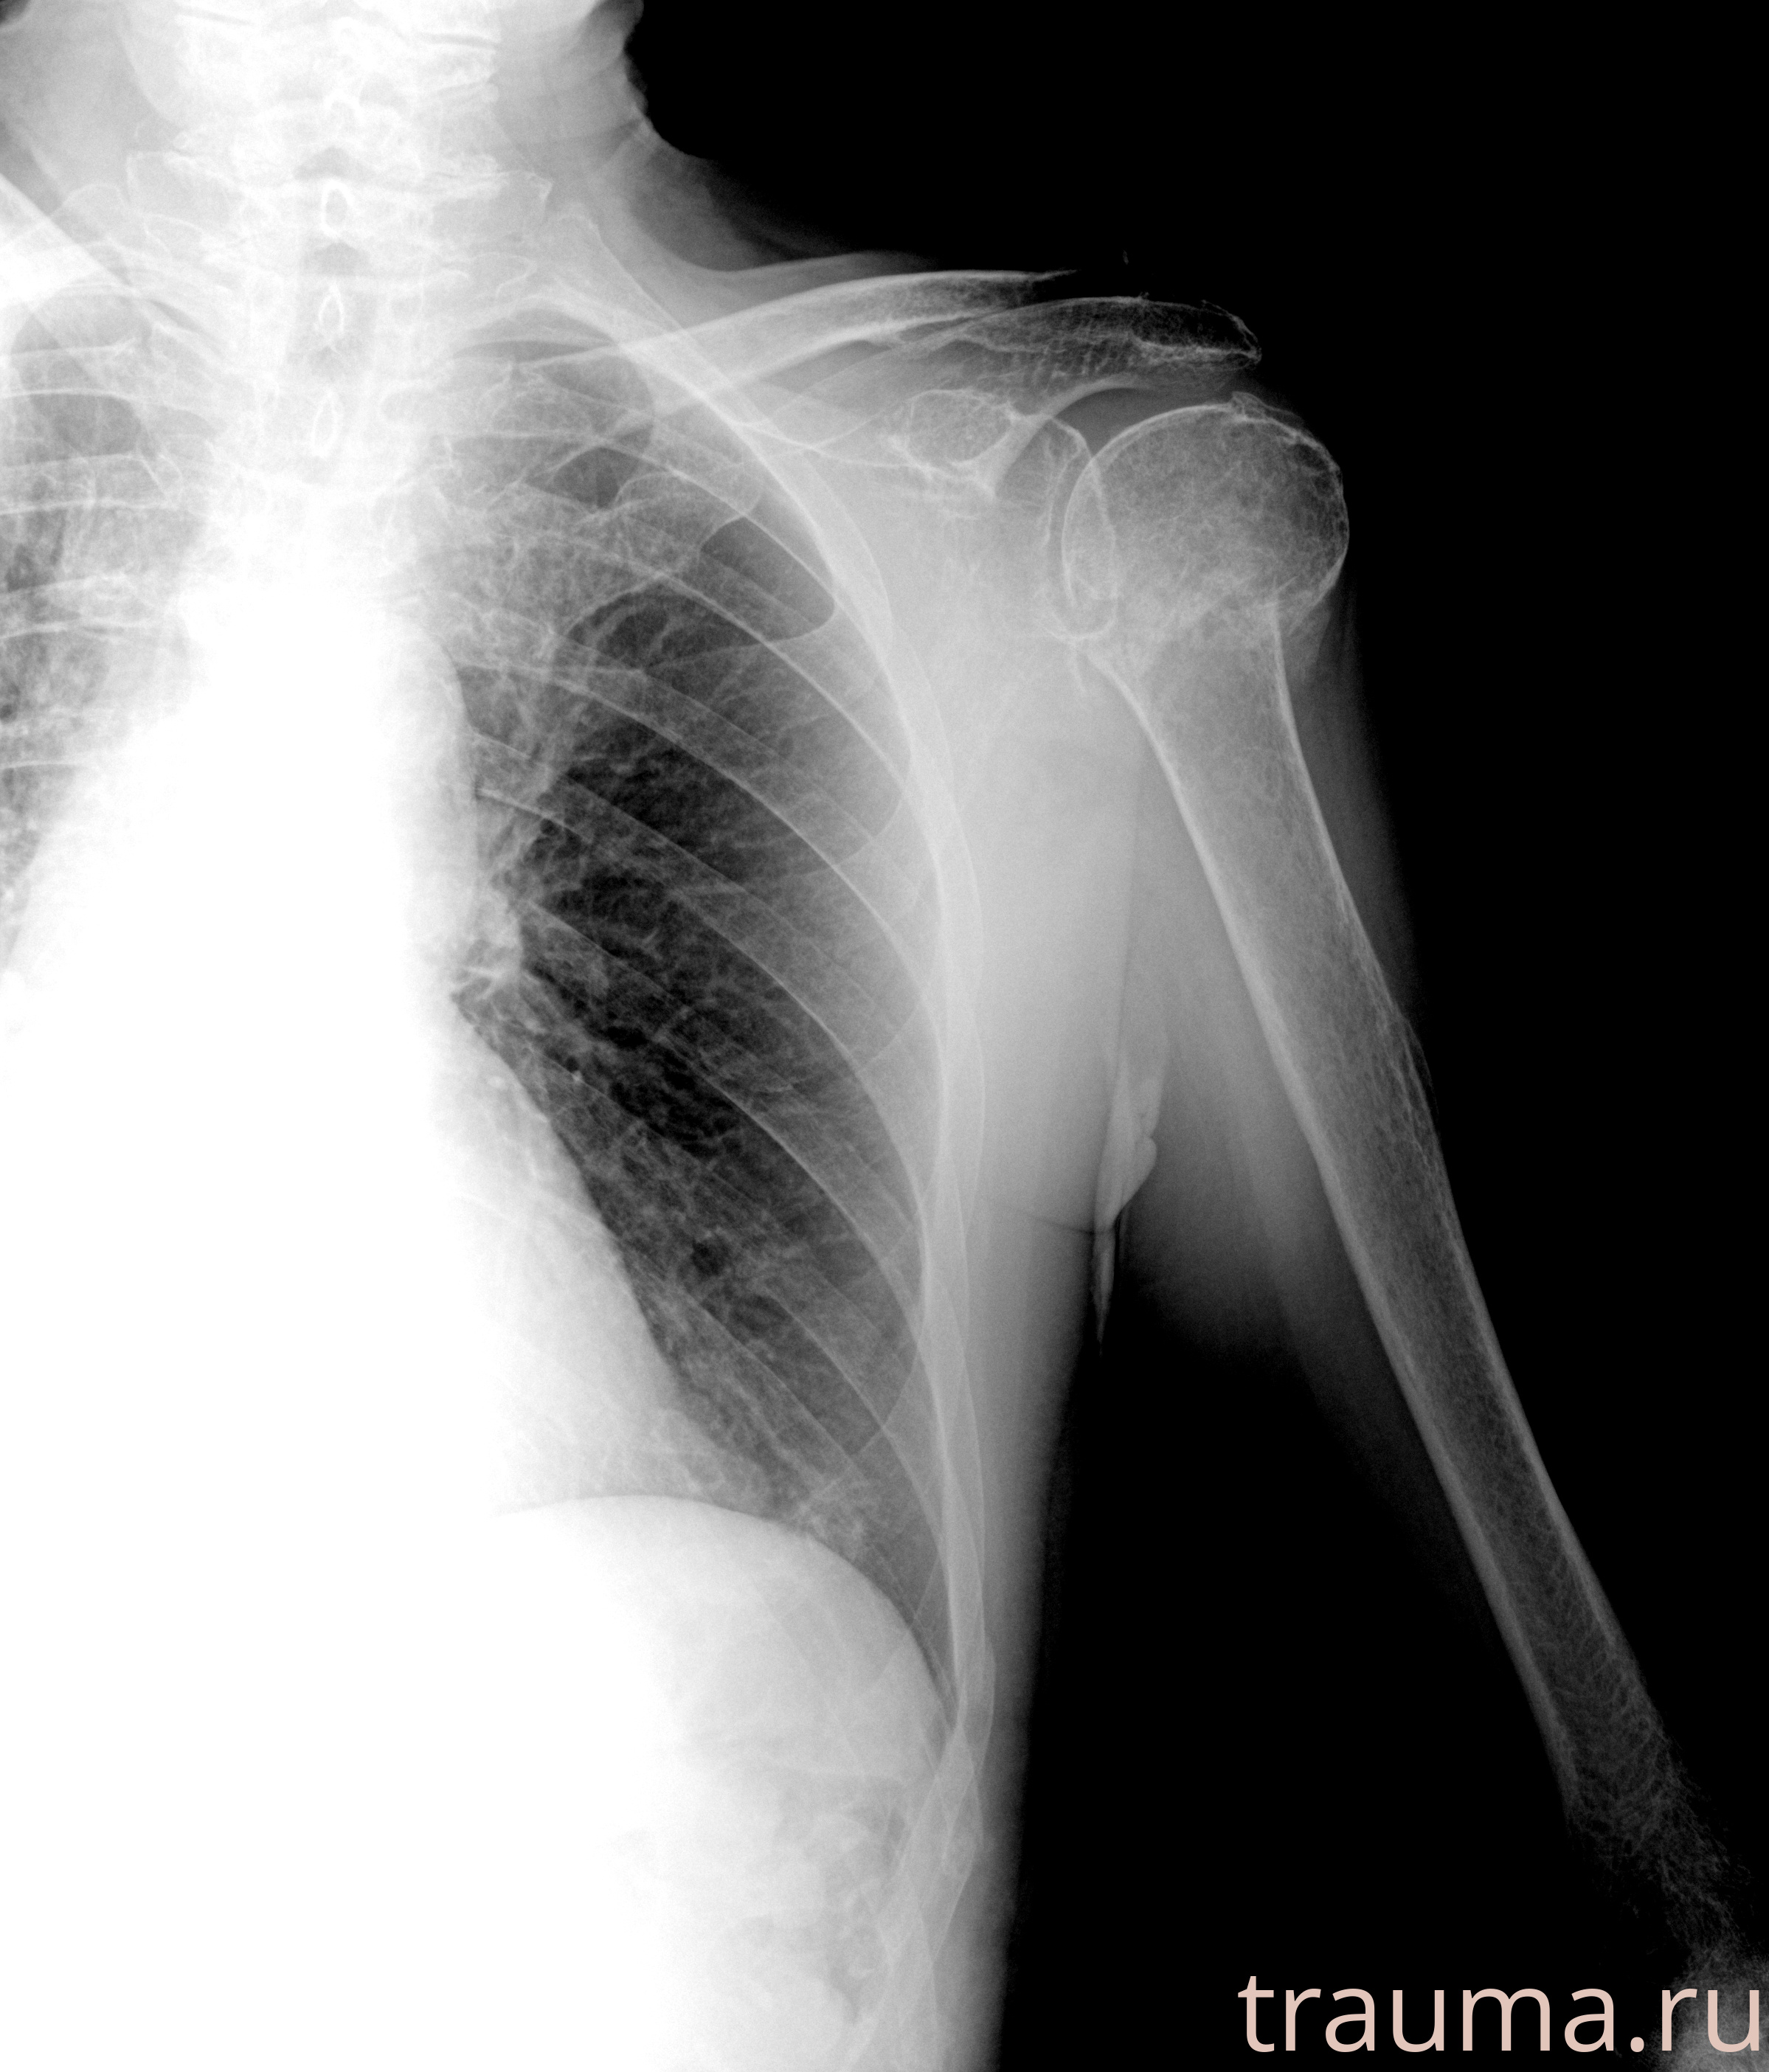

Рентген на дому: по вашему адресу приезжает врач-рентгенолог, травматолог-ортопед с мобильным рентгеновским аппаратом, проводит диагностику травмы или заболевания, делает необходимые рентгенограммы, дает рекомендации по дальнейшему лечению. Получить качественные снимки в домашних условиях возможно благодаря уникальной методике, разработанной МосРентген Центром для института  Склифосовского

при переломе шейки бедра и пневмонии от компании МосРентген Центр - партнера Института имени Склифосовского